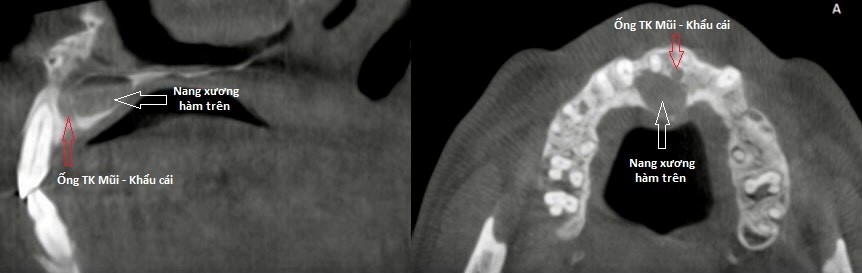

Người bệnh nhập viện trong tình trạng đau vùng vòm miệng tương ứng răng cửa hàm trên khoảng 1 tháng nay, niêm mạc vòm miệng nề đỏ, ấn có dịch chảy ra từ rãnh lợi. Qua thăm khám, bác sĩ chẩn đoán người bệnh có nang xương hàm trên vùng vòm miệng. Sau khi hội chẩn các Bác sĩ đã tiến hành chỉ định phẫu thuật cắt nang xương hàm trên, bảo tồn ống thần kinh mũi – khẩu cái. Ca phẫu thuật diễn ra trong thời gian 60 phút. Hiện người bệnh đang được điều trị hậu phẫu, sức khoẻ ổn định.